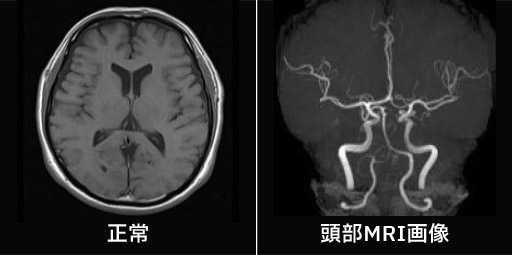

頭部MRI検診のご案内

くも膜下出血の原因となる動脈瘤、認知症に関係する脳萎縮、脳梗塞を引き起こす脳血管の異常など、自覚症状がない脳の異常を調べます。脳の状態を調べる

脳の断面像を撮影することで、脳梗塞や脳出血、水頭症、脳萎縮などの異常を発見することが出来ます。脳の血管を調べる

血管を立体的に画像化することで、未破裂脳動脈瘤や脳動脈の狭窄などの異常を発見することが出来ます。なお造影剤は使用しません。